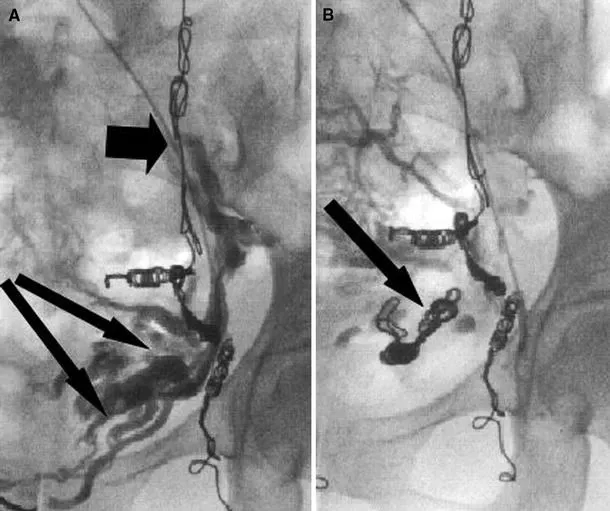

图:(a)静脉超声显示右腹股沟隐筋膜内的原发性瓣膜静脉曲张畸形(PAVA)组织- 大隐静脉 (GSV) 和前副隐静脉 (AASV) 先前消融-箭头显示不同的PAVA血管。(b)同一患者显示PAVA进出一个淋巴结。

图:a 大隐静脉剥脱术后1年大腿剥除处血管再生的纵向超声图像。注意存在多个管道。b 彩色血流多普勒图像显示剥除处血管再生大腿上每个管道都有反流。

图:大隐静脉剥脱术后1年大腿血管再生的横向超声图像,四个管道可见。

显示腿部近端静脉和右髂内静脉分支之间的沟通。

(A)左卵巢静脉栓塞(短箭头)。反流扩张的髂内静脉属支(长箭头)。(B)栓塞的左髂内静脉血流停止(箭头)。

(A)迷走左腰静脉线圈(箭头)。如果没有选择性栓塞,这将继续充盈左卵巢静脉,并导致持续的反流。(B)栓塞后的左右卵巢静脉(长箭头)和迷走的左腰静脉(短箭头)。